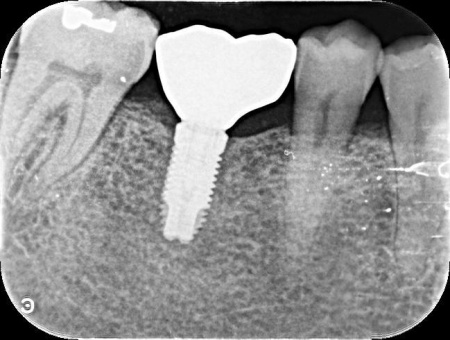

| 診断 | 拝見したところ、左下奥歯(第1大臼歯)が抜けており、見た目が気になるだけでなく奥歯でしっかりと噛むことが難しくなっていました。 このまま放置すると食事の際に支障が出たり、噛み合わせのバランスが崩れて残っているほかの歯に影響を及ぼしたりする可能性があります。 以上のことから、抜けた歯を補い見た目と噛む機能を回復させる治療が必要と診断しました。 |

| 行ったご提案・治療内容 | 患者様はあごの骨に人工歯根を埋め、その上に人工歯を装着するインプラント治療を希望されています。 インプラント治療は自分の歯のような自然な見た目と噛み心地が期待できる一方で、自費診療のため費用が高くなることや外科処置を伴うため身体的負担がかかること、治療期間が比較的長くなる点がデメリットです。 また、安定したインプラント治療を行うためにはインプラントを支えられるあごの骨が残っているか、インプラントの上に人工歯を取り付けた際に噛み合わせの歯が邪魔をしないかなどを確認する必要があります。 その結果、十分な骨の量があり、噛み合わせの歯もインプラントを入れた際に自然に噛める位置に生えていたため、インプラント治療を行う条件は問題ないと判断しました。 【治療手順】 最後に見た目や噛み合わせに問題がないことを確認し、治療を終了しました。 |